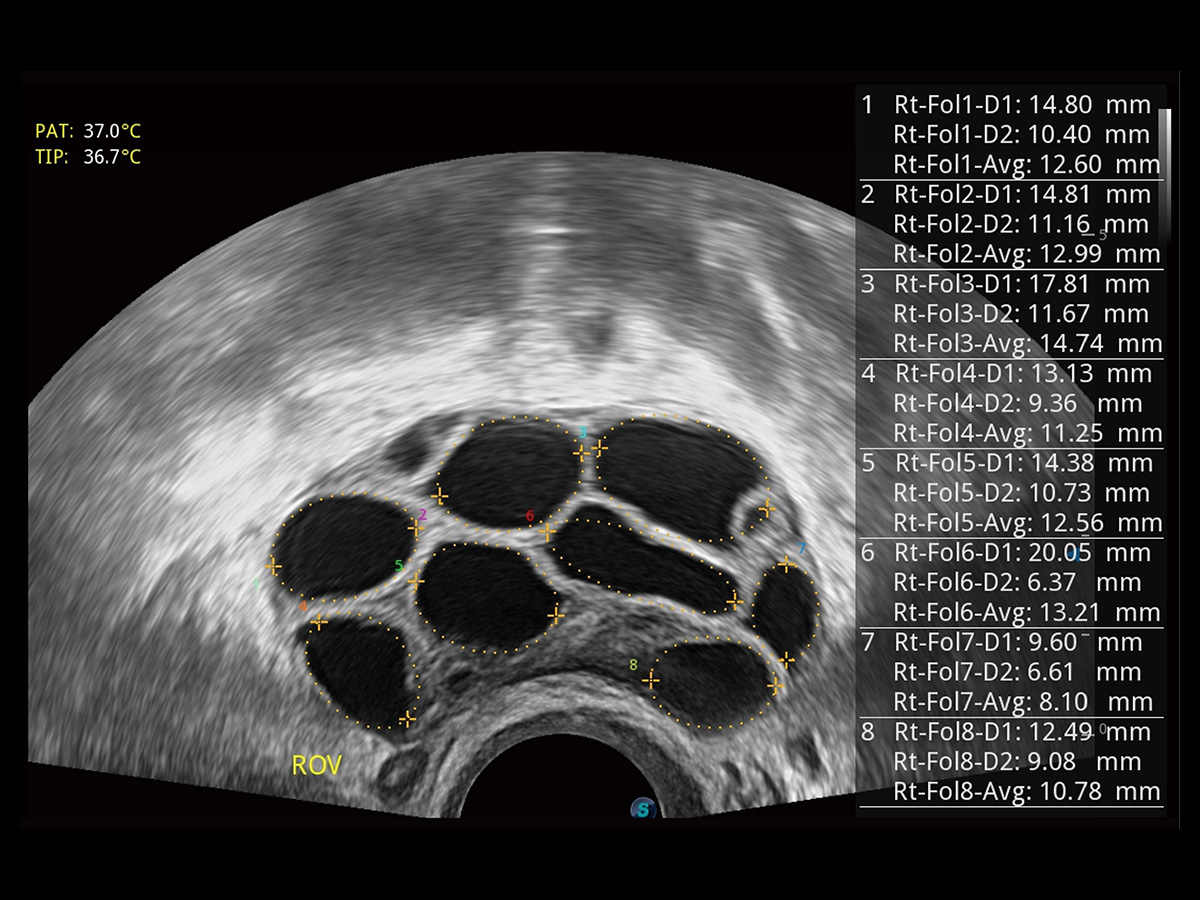

“生育问题”即关系民族复兴,也关系亿万家庭的幸福。随着婚育年龄推迟、社会压力增加等因素,越来越多人群也面临着“生不出、生不好”的问题。辅助生殖作为治疗不孕不育最有效的方法之一,也逐渐成为育儿新希望。而超声检查能为生殖需求人群的初诊评估提供宝贵的信息。 P20 Elite是开立医疗匠心打造的一款生殖应用型彩超。她继承开立医疗高端极光平台,突破性地将多款新型芯片及硬件模块进行整合,均衡了高端系统性能与小巧灵动机身。P20 Elite卓越的图像质量搭载专科探头,旨在为您提供全面的辅助生殖解决方案。

P20 Elite配备了丰富的生殖探头群和临床应用功能,在卵泡监测、穿刺取卵、胚胎移植、妊娠确认等领域,为生殖需求人群提供了新的临床机会,重新定义高端超声如何应用于生殖健康检查。

通过线上云会诊平台,实现县级医院与上级医院患者卵泡数据互联互通。避免重复性卵泡测量,提高诊断效率。